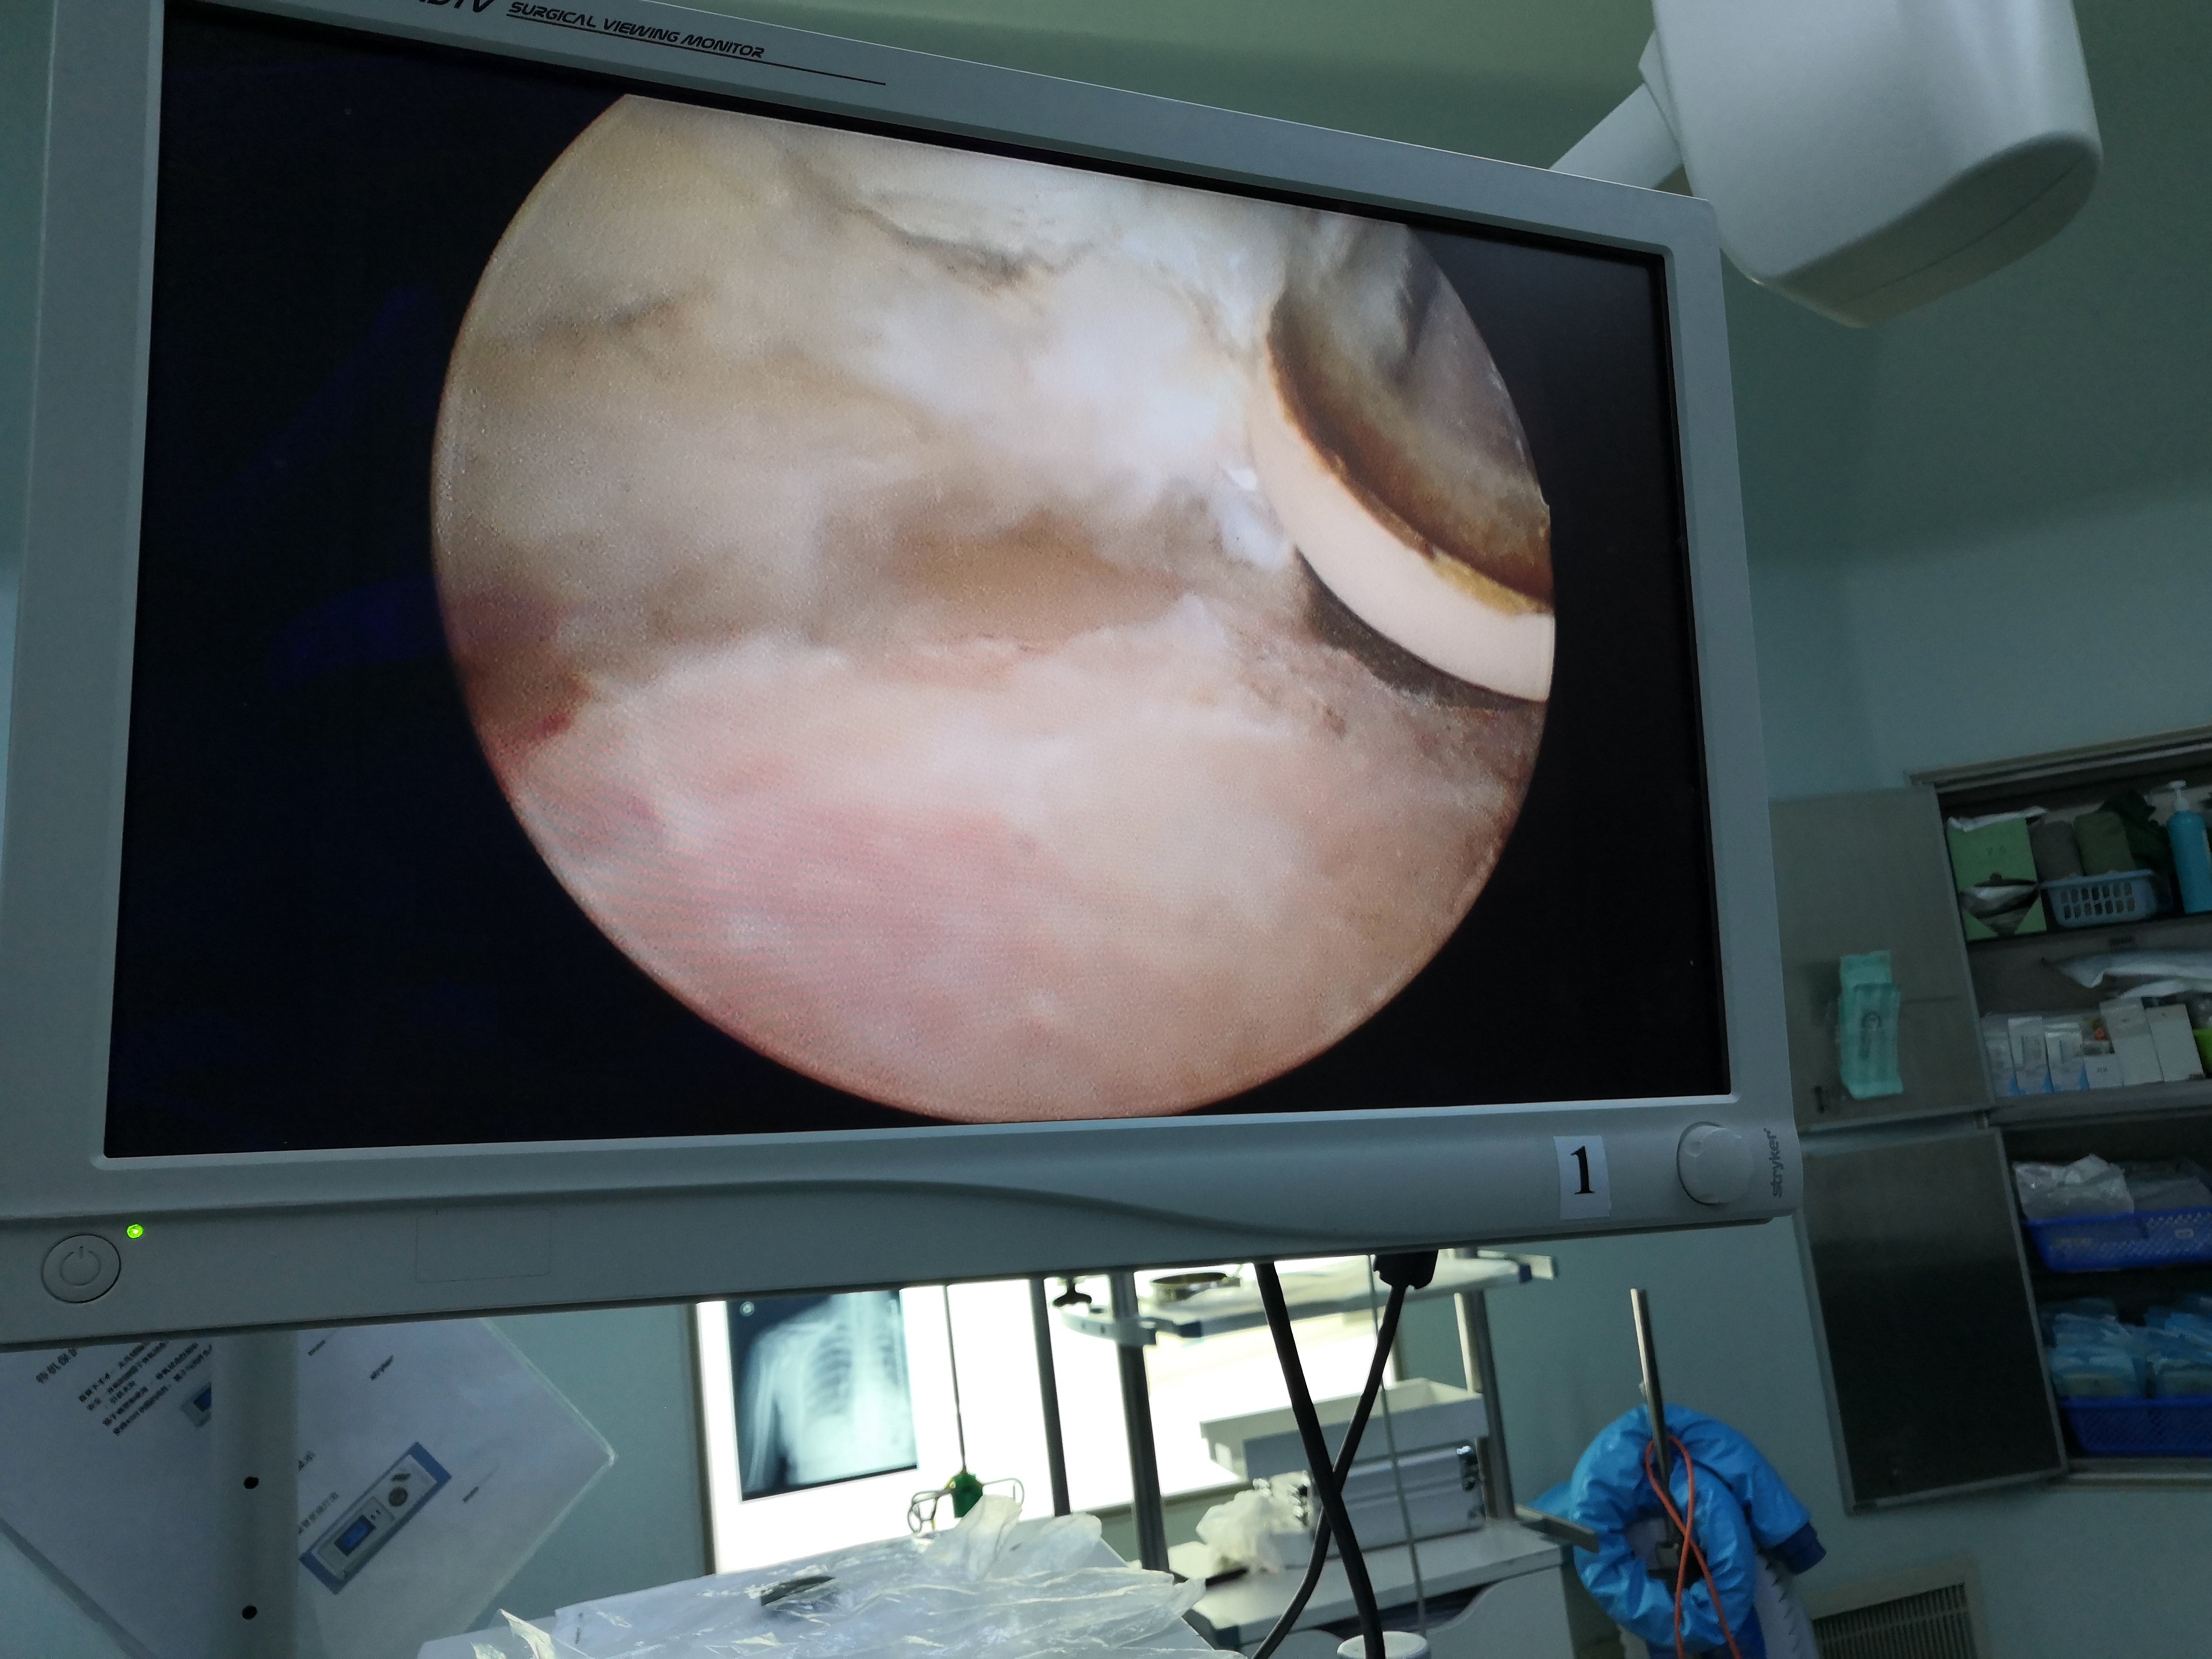

关节镜下治疗钙化性岗上肌钙化性肌腱炎

关节镜下冈下肌腱巨大钙化灶清理,肌腱缝合修补术